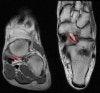

8. Achilles tendon

Axial T1W image assessing the normal Achilles tendon (red). Normally the Achilles tendon is concave or flat on axial imaging.

If it is convex or if it is >6 mm it is abnormal. Incidental accessory soleus muscle (green)